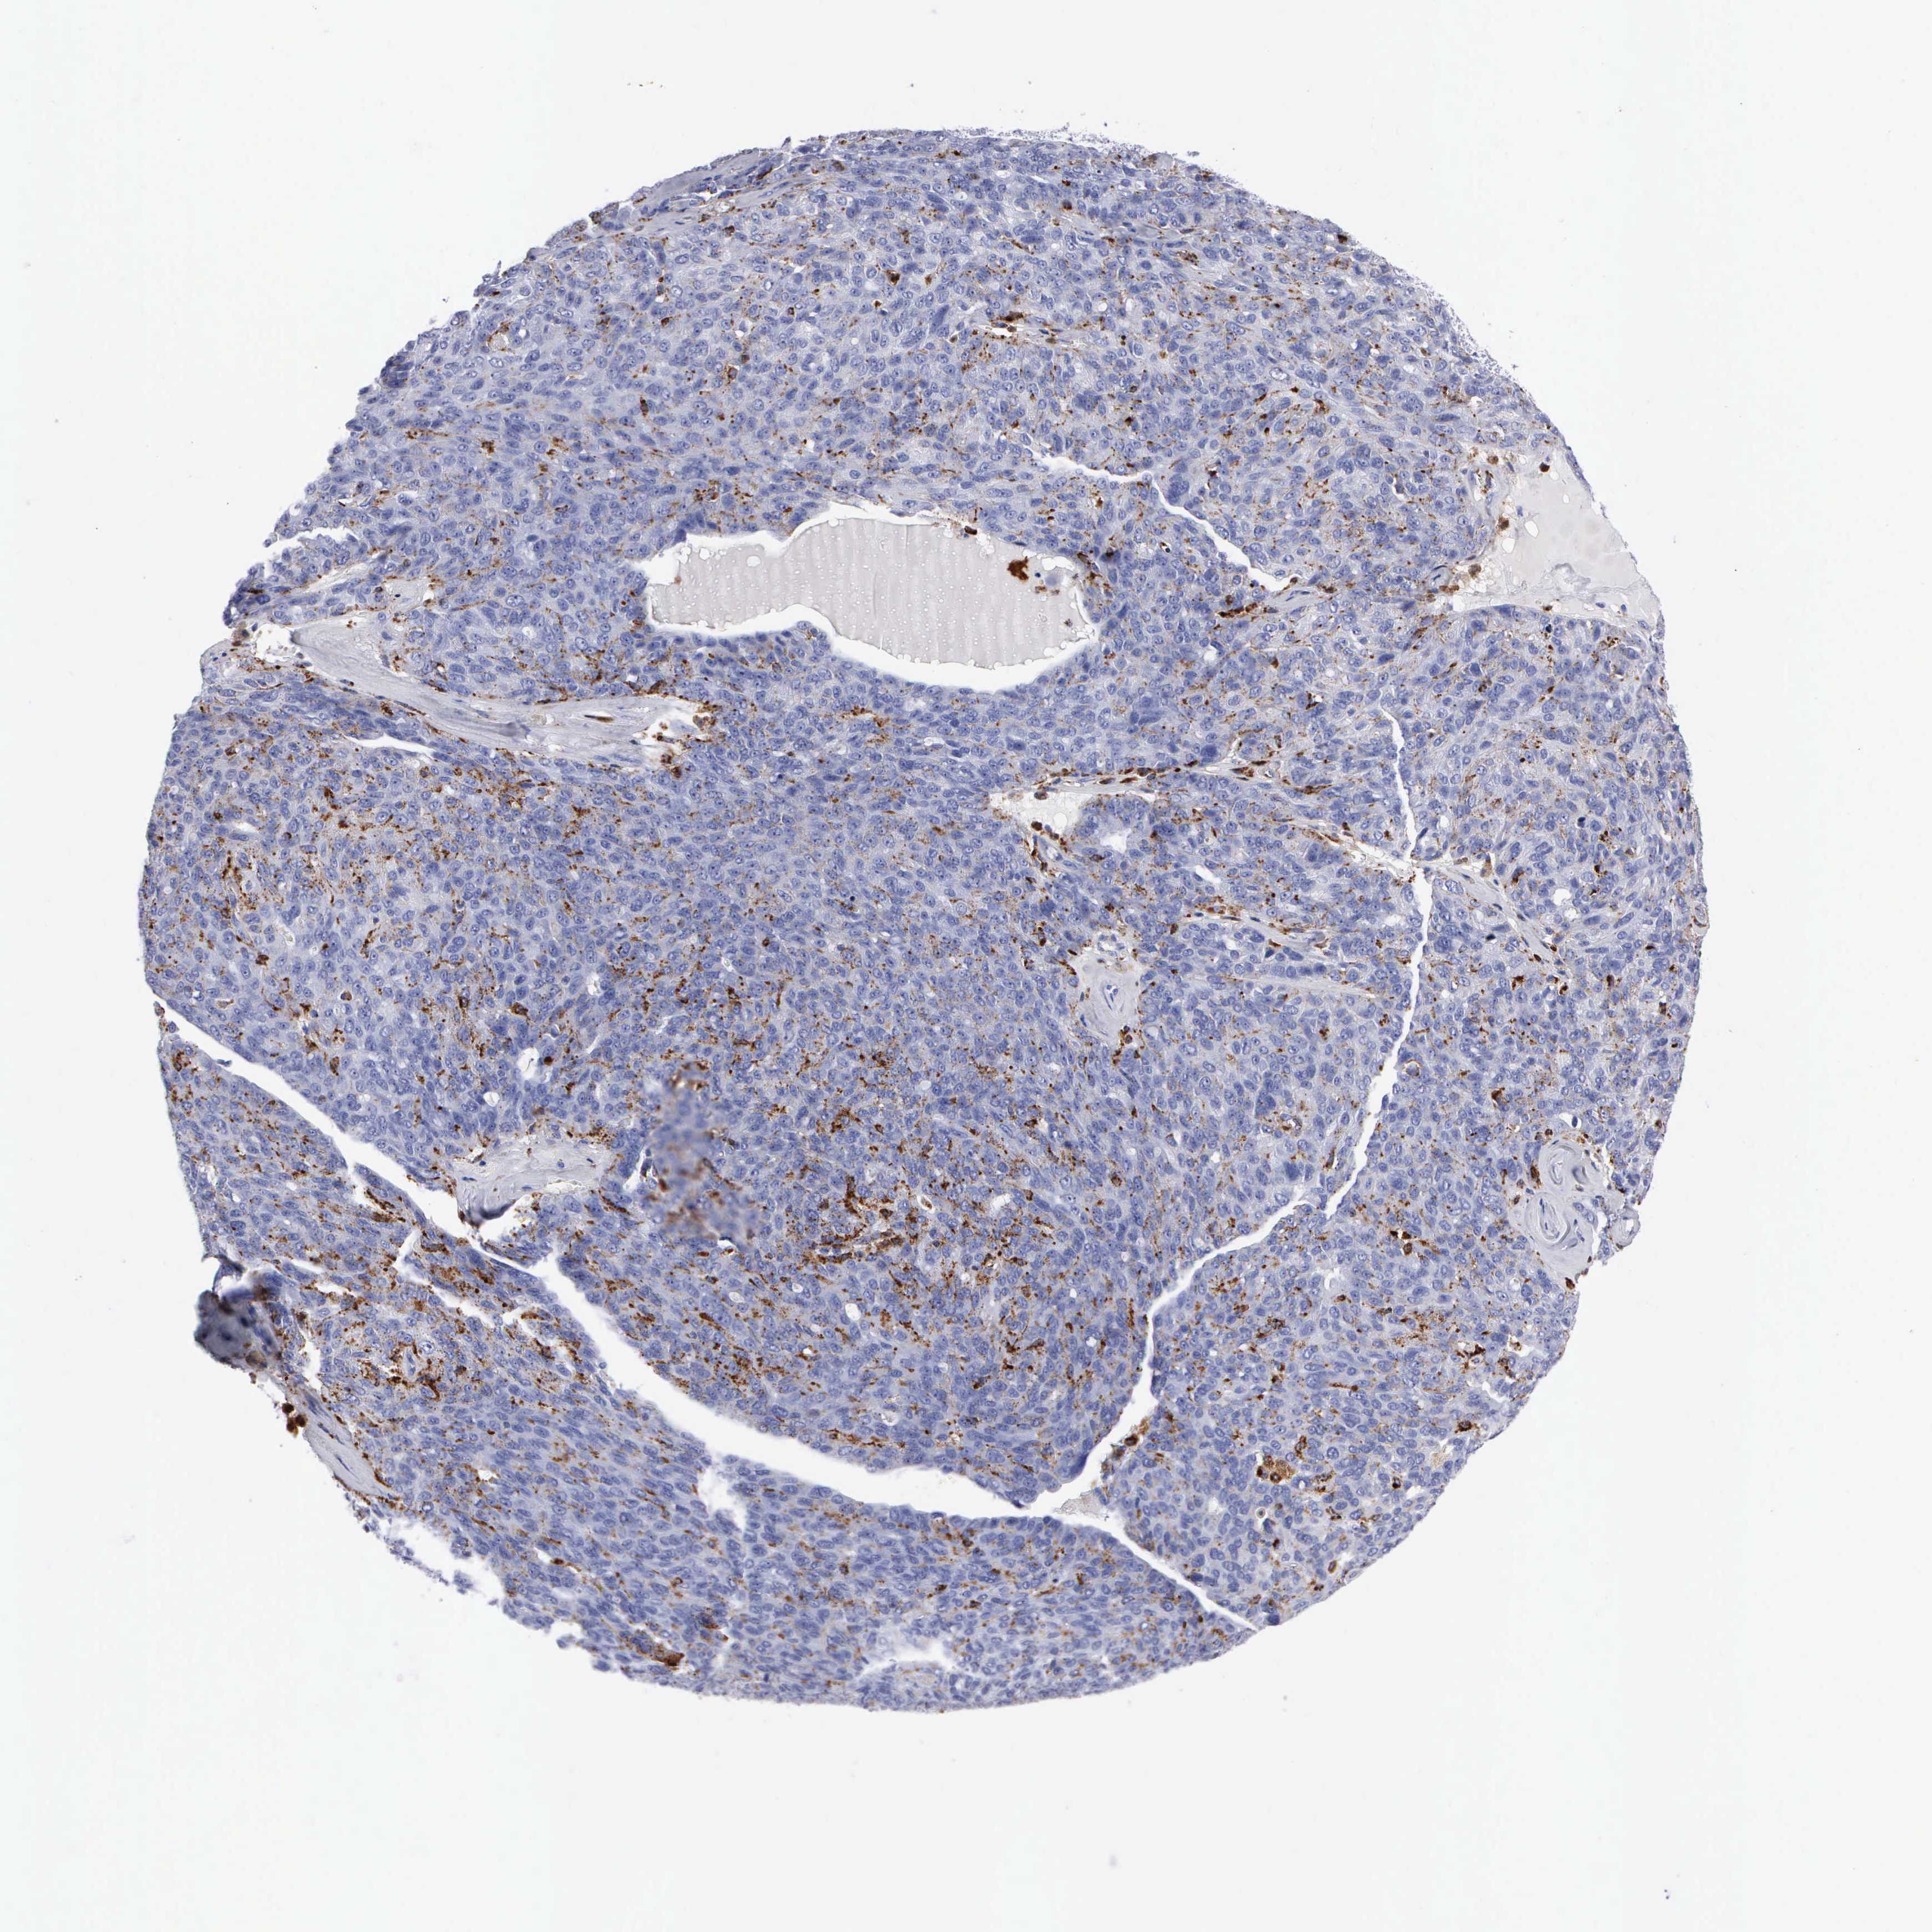

OVARIAN CANCER - Protein expressioni

A mouse-over function shows sample information and annotation data. Click on an image to view it in a full screen mode. Samples can be filtered based on level of antibody staining by selecting one or several of the following categories: high, medium, low and not detected. The assay and annotation is described here.

Note that samples used for immunohistochemistry by the Human Protein Atlas do not correspond to samples in the TCGA dataset.

Antibody stainingi

Antibody staining in the annotated cell types in the current human tissue is reported as not detected, low, medium, or high, based on conventional immunohistochemistry profiling in selected tissues. This score is based on the combination of the staining intensity and fraction of stained cells.

Each image is clickable and will lead to virtual microscopy that enables deeper exploration of all samples and also displays staining intensity scores, fraction scores and subcellular localization as well as patient and tissue information for each sample.

Antibody CAB000458

Cystadenocarcinoma, serous, NOS